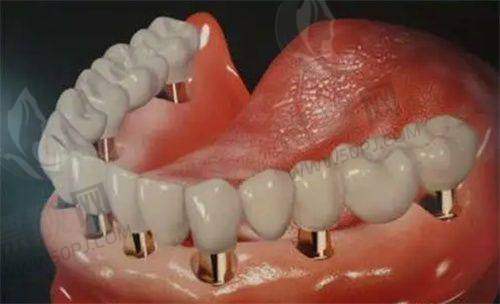

项目参考价格:种植牙3000元起,韩系种植3500元起,全口种植约10万起。

成功实例:邻居王阿姨原来怕假牙松动,这次在牙世佳做了五颗种植,医生每天跟进,每月复查一次,如今吃牛排都轻松。